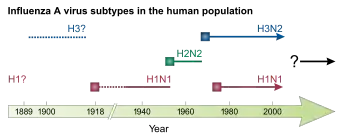

Influenzavirus A

This genus has one species, influenza A virus. Wild aquatic birds are the natural hosts for a large variety of influenza A.[40] Occasionally, viruses are transmitted to other species and may then cause devastating outbreaks in domestic poultry or give rise to human influenza pandemics.[40] The influenza A virus can be subdivided into different serotypes based on the antibody response to these viruses.[41] The serotypes that have been confirmed in humans are:

- H1N1, which caused Spanish flu in 1918, and Swine Flu in 2009

- H2N2, which caused Asian Flu in 1957

- H3N2, which caused Hong Kong Flu in 1968

- H5N1, which caused Bird Flu in 2004[42][43]

- H7N7, which has unusual zoonotic potential[44]

- H1N2, endemic in humans, pigs and birds

- H9N2

- H7N2

- H7N3

- H10N7

- H7N9, rated in 2018 as having the greatest pandemic potential among the Type A subtypes[45]

- H6N1, which only infected one person, who recovered[46]

New influenza viruses are constantly evolving by mutation or by reassortment.[41] Mutations can cause small changes in the hemagglutinin and neuraminidase antigens on the surface of the virus. This is called antigenic drift, which slowly creates an increasing variety of strains until one evolves that can infect people who are immune to the pre-existing strains. This new variant then replaces the older strains as it rapidly sweeps through the human population, often causing an epidemic.[194] However, since the strains produced by drift will still be reasonably similar to the older strains, some people will still be immune to them. In contrast, when influenza viruses reassort, they acquire completely new antigens—for example by reassortment between avian strains and human strains; this is called antigenic shift. If a human influenza virus is produced that has entirely new antigens, everybody will be susceptible, and the novel influenza will spread uncontrollably, causing a pandemic.[195] In contrast to this model of pandemics based on antigenic drift and shift, an alternative approach has been proposed where the periodic pandemics are produced by interactions of a fixed set of viral strains with a human population with a constantly changing set of immunities to different viral strains.[196]